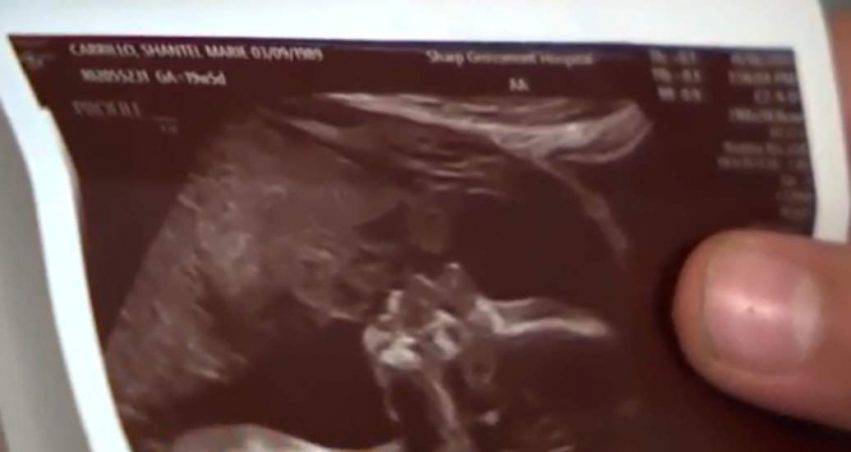

Una mamma ha visto un volto nell’ecografia della figlia.

Shantel Carillo è una mamma che sostiene di aver visto il volto di un uomo nell’ecografia della figlia, ancora nella sua pancia.

Una mamma incinta vede un volto che bacia la figlia nell’ecografia dopo una visita

Stando a quanto la donna ha riferito ad Abc7 lei ritiene di intravedere perfettamente il volto del nonno della piccina comprese le guance e le labbra. Addirittura Shantel ha visto anche un cappello che l’uomo usava indossare. Quando Shantel ha condiviso lo scatto in tanti hanno osservato: “ah sembra che qualcuno stia baciando la tua bambina”. La mamma allora ha osservato la foto e ha notato che non era qualcuno, ma era il padre morto.

Per lei l’immagine non è strana o inquietante, anzi, lei ci vede qualche messaggio. Suo padre Charles detto Chuck purtroppo è morto nel 2016 e non sarà vicino alla nipotina per vederla crescere. Secondo lei questa foto è il segnale che l’uomo dall’alto continua ad essere vicino a sua figlia e i suoi bambini. La donna aggiunge: “è carina da guardare e una grande storia da raccontare”.

“Ho trovato un’immagine di mio padre che guarda mia figlia nello stesso modo in cui guardava gli ultrasuoni ed è come se l’avessi preso in pieno”. La mamma prosegue: “ha il suo naso, le sue piccole guance piene, il doppio mento. Oltretutto mio papà indossava un cappotto come quello, le sue labbre toccano mia figlia perfettamente“. L’immagine è di conforto per questa mamma che attende la sua seconda figlia per il 2020. “Mio papà sarebbe molto felice, sento come se lui cercasse di includersi in qualche modo”.